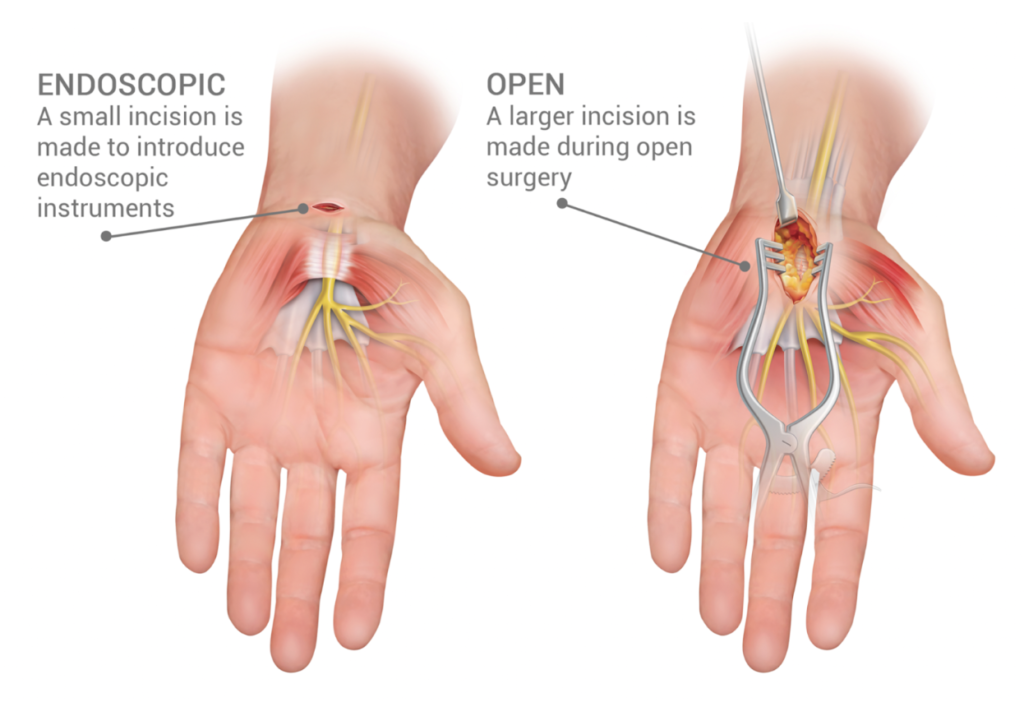

Peripheral Nerve Surgery

Diagnosis and surgical treatment of peripheral nerve disorders aim to relieve pain and restore function.

Management of nerve compression, injury, and tumours.

Procedures focused on protecting nerve integrity while improving mobility and quality of life.